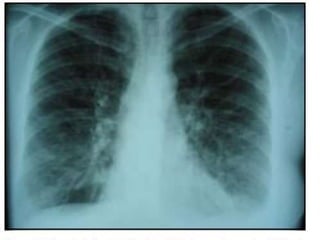

• PLEUROPULMONAR (más en hombres)

• Pleuritis con derrame pleural

• Fibrosis intersticial con alteración de la DLCO

• HT Pulmonar (raro).

• Bronquiolitis obliterante.

• Nódulos: cavitación, fístulas, neumotórax.

• Síndrome de CAPLAN: AR + neumoconiosis